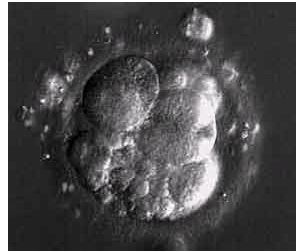

Bb эмбрионы

Bb эмбрионы 115 фото